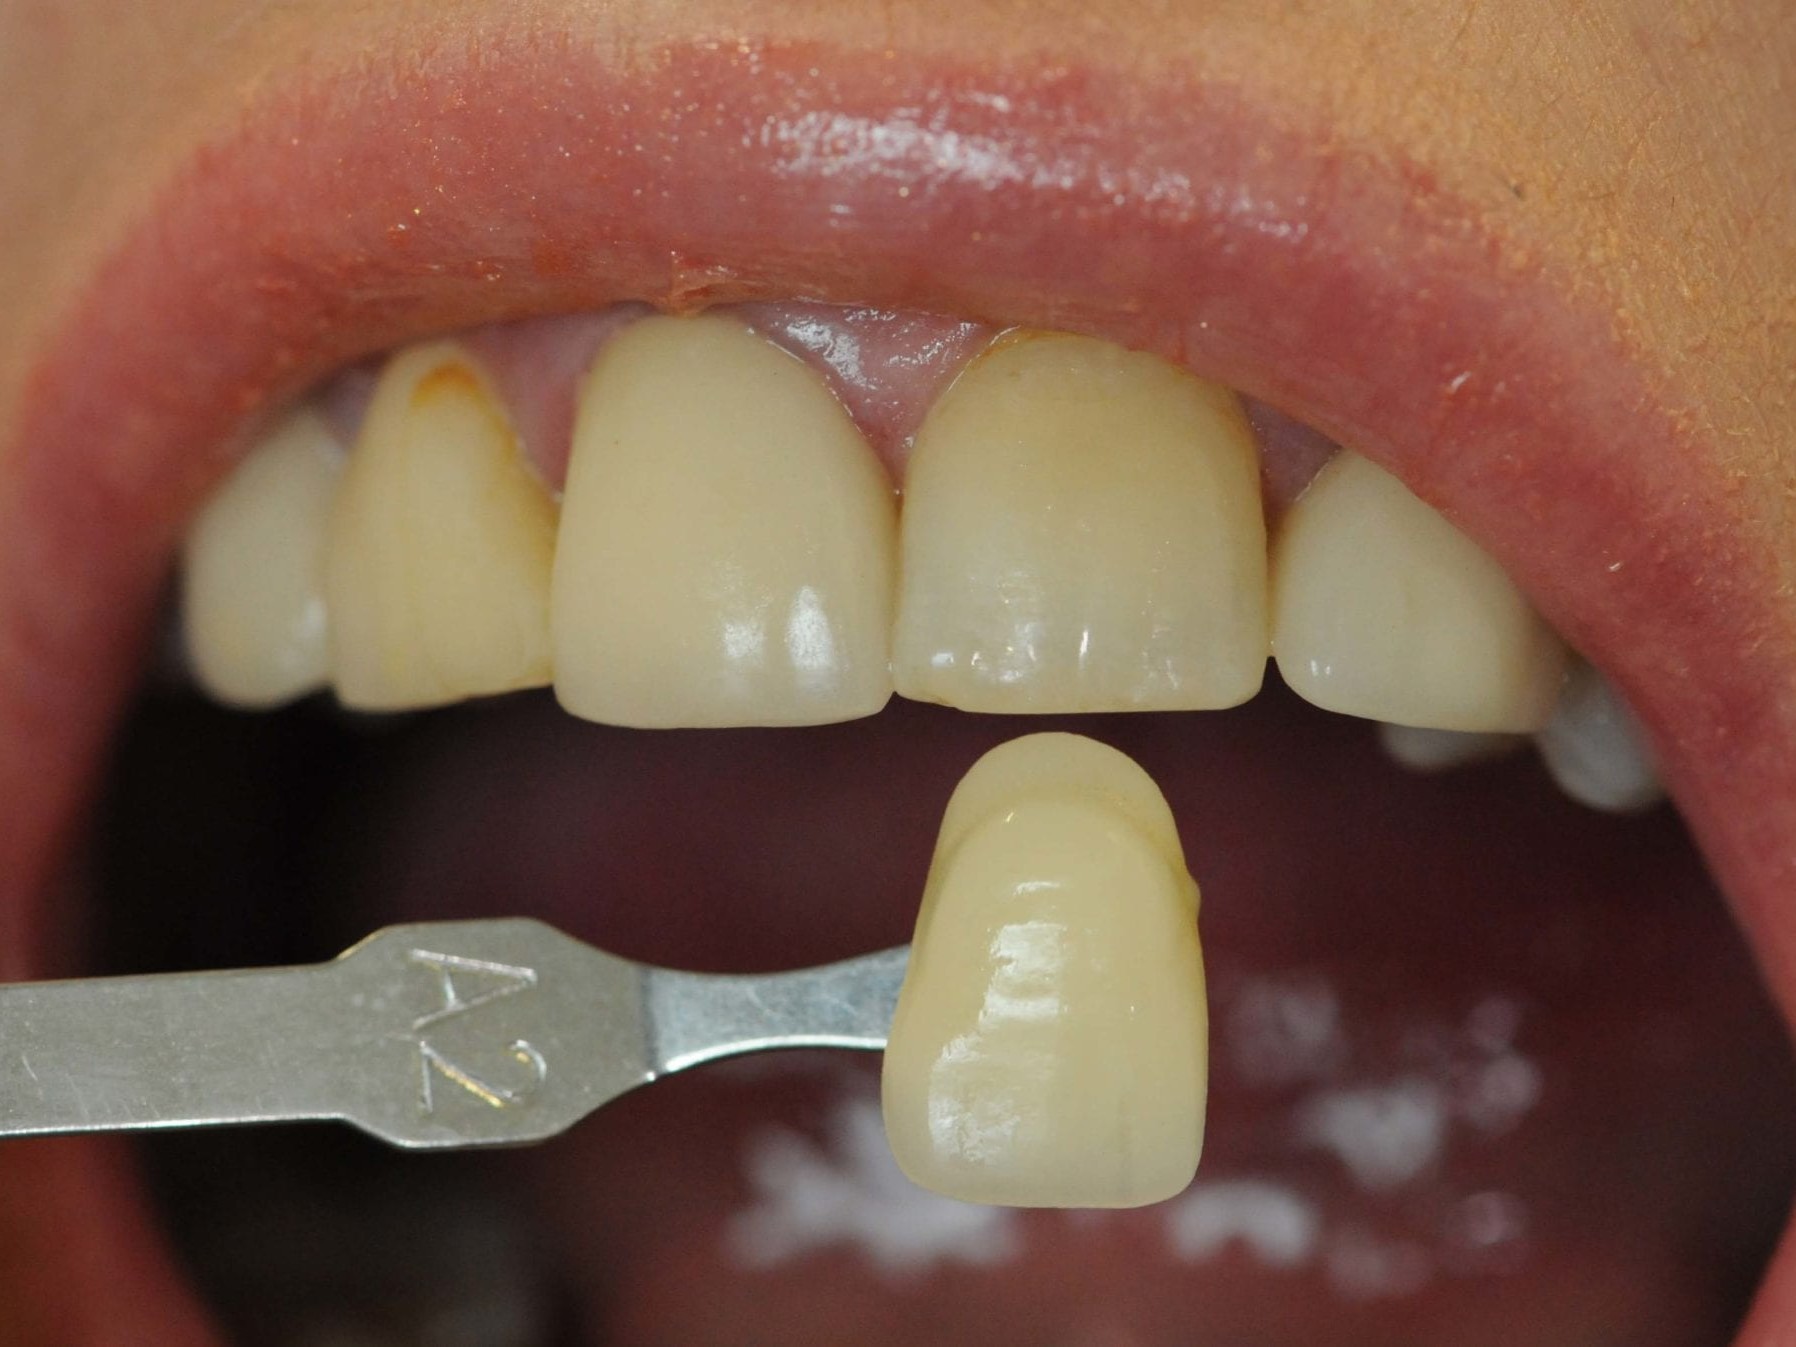

Abb 2 Klinische Ausgangssituation mit Farbwahl

Abb. 2: Klinische Ausgangssituation mit Farbwahl

Die Patientin war seit Jahren mit einer Brückenversorgung gut rehabilitiert. In der Frontzahnregion sollte die frakturierte Zirkonbrücke erneuert werden (Abb. 1 und 2). In der Molarenregion war die Entfernung des Zahnes 25 in Erwägung gezogen worden, um eine erneute Brückenversorgung durchzuführen. Dieses war aber nur mit der Präparation eines weiteren gesunden Zahnes zu erzielen. Eine Implantatversorgung wurde der Patientin nicht offeriert. Die Neuversorgung des Oberkiefers mit einer weiteren Hinzuziehung von gesunden Nachbarzähnen im Sinne einer konventionellen zahnärztlichen Lösung sah die Patientin als nicht mehr zeitgemäß an. So stellte sich die Patientin in unserer Praxis vor.